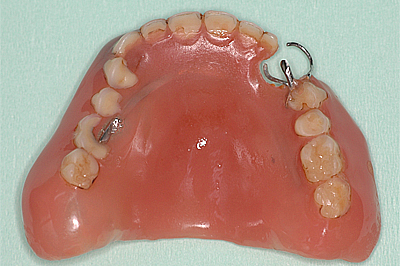

16年間使っている義歯